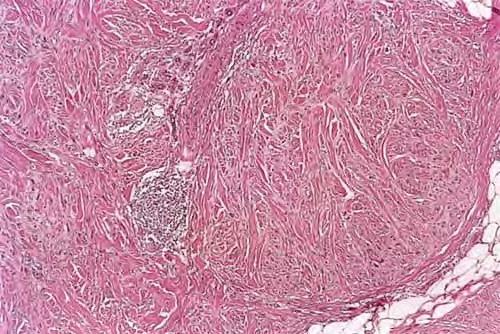

Desmoplastic melanoma = الميلانوم المكون للالتصاقات